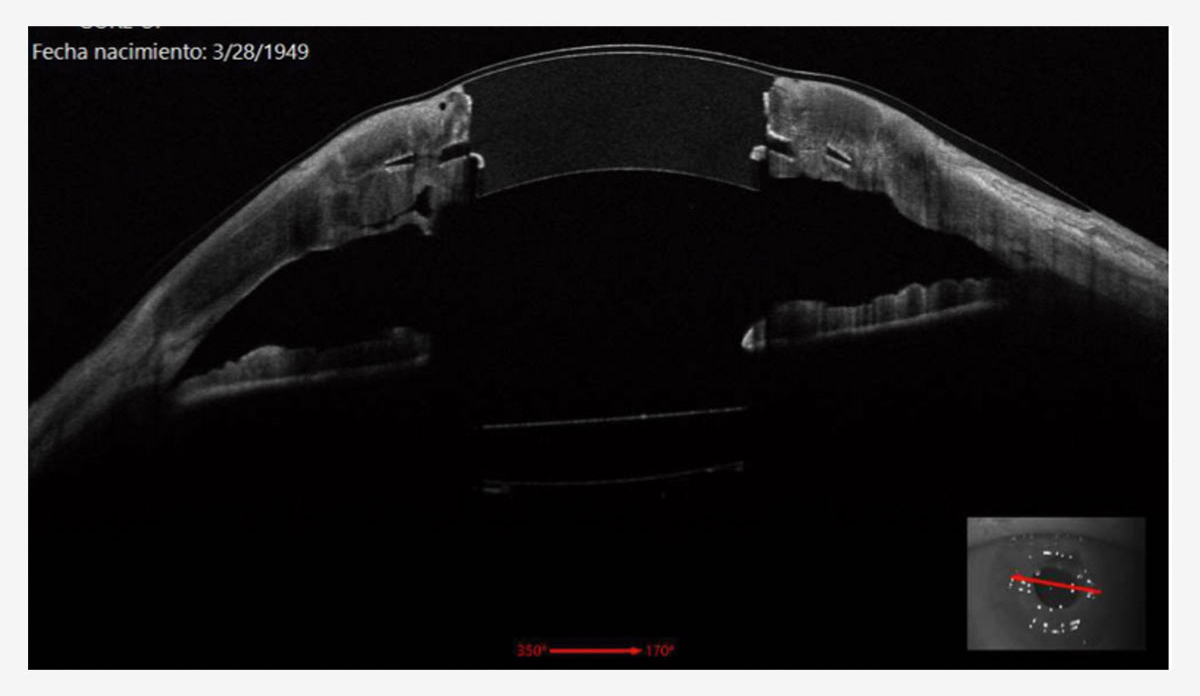

Figura 2. OCT de segmento anterior dispositivo sintético corneal de Gore. Un año después de su implante.

La técnica de implantación es modificada de la técnica usada en conejos y utiliza anestesia general y un tomógrafo de coherencia óptica (OCT) intraoperatorio. Se sutura un anillo de Flieringa y se trepana parcialmente una porción de 4 a una profundidad aproximada de dos tercios del grosor corneal. Se realiza un bolsillo intraestromal de 360° usando una cucharilla angulada de doble bisel. Es importante dejar un grosor de una lamela anterior entre 200 a 400 micras. Se realiza una paracentesis y se ingresa viscoelástico a cámara anterior. Se realiza una escisión del botón corneal con diámetro de 4 mm usando tijeras tras profundizar la trepanación inicial. El dispositivo de Gore es introducido con un fórceps y rotado usando un Sinskey. Esto permite maniobrar la falda flexible del dispositivo hasta estar 360° dentro del bolsillo estromal sin doblar. Se confirma la posición del dispositivo mediante el uso de OCT intraoperatorio. Se sutura el dispositivo con 16 suturas interrumpidas de nylon 10-0 del tejido corneal receptor al centro del dispositivo para evitar retracción del centro óptico. Se irriga la cámara anterior con solución salina balanceada para eliminar el viscoelástico y evitar picos hipertensivos.